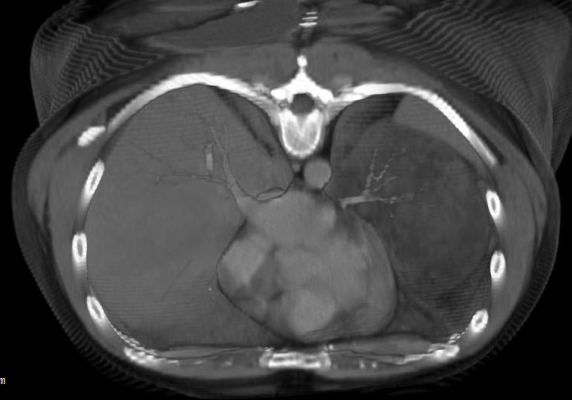

October 21, 2020 — The BBC News reported that Luke Allard of Mill Houses, King's Lynn, died at Queen Elizabeth Hospital in March one day after being discharged. Allard, 28, had Marfan syndrome, a genetic disorder that can cause heart issues. BBC reported that an inquest was heard after he was discharged when another patient's computed tomography (CT) image was looked at in error. He was recalled to the hospital once the mistake was realized the following morning, but died soon after arrival. He suffered a cardiac arrest due to a ruptured aortic aneurysm. According to the area coroner, Allard had been awaiting heart surgery at Papworth Hospital in Cambridge.